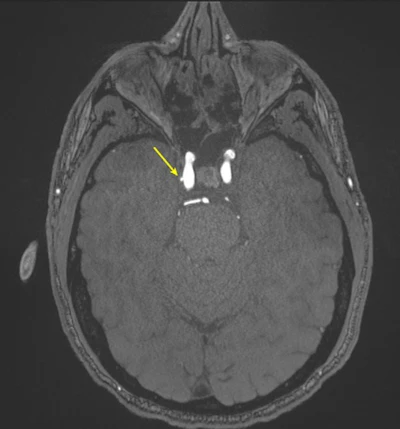

Representative axial time-of-flight MR angiography image in a 39-year-old male participant shows a laterally projecting intracranial aneurysm (arrow) originating from the right cavernous segment of the internal

carotid artery.RSNA